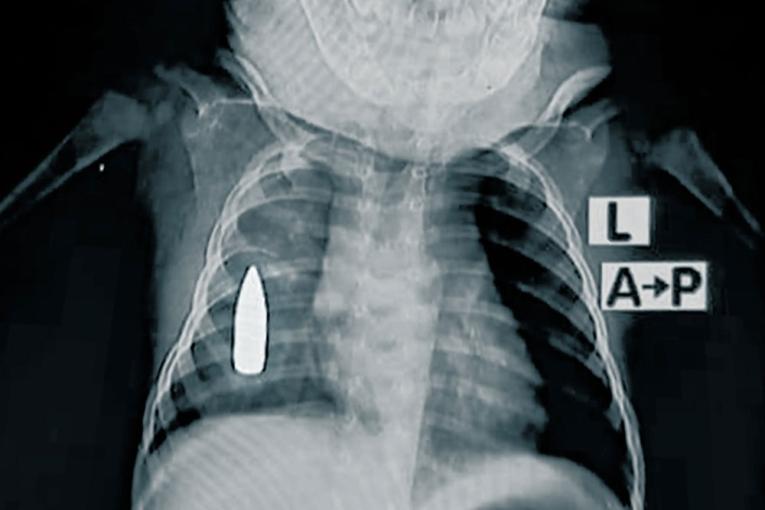

Radiographie de Riyad. L'enfant de 18 mois a été touché à la poitrine par une balle perdue alors qu'il faisait une sieste à Khartoum. © MSF

Riyad, 18 mois, est l'un des 314 enfants soignés pour des blessures par balle ou par explosion cette année. « Riyad a été amené aux urgences après avoir été touché au côté droit par une balle perdue alors qu'il faisait la sieste dans la maison familiale », explique le Dr Moeen1 , responsable de l'équipe médicale de MSF. « L'équipe médicale a tenté de le stabiliser pendant quatre heures. En raison de l'importante perte de sang, il y avait une chance sur deux pour qu'il ne survive pas à l'opération ».

L'équipe a réussi à arrêter l'hémorragie, mais la balle est restée logée dans sa poitrine. L'hôpital ne dispose pas de capacités chirurgicales avancées, en partie à cause d'un blocage systématique de l'envoi de matériel chirurgical depuis octobre 2023. Il est également très difficile d'envoyer des patients hors de la zone, car les routes sont soit détruites, soit beaucoup trop dangereuses.